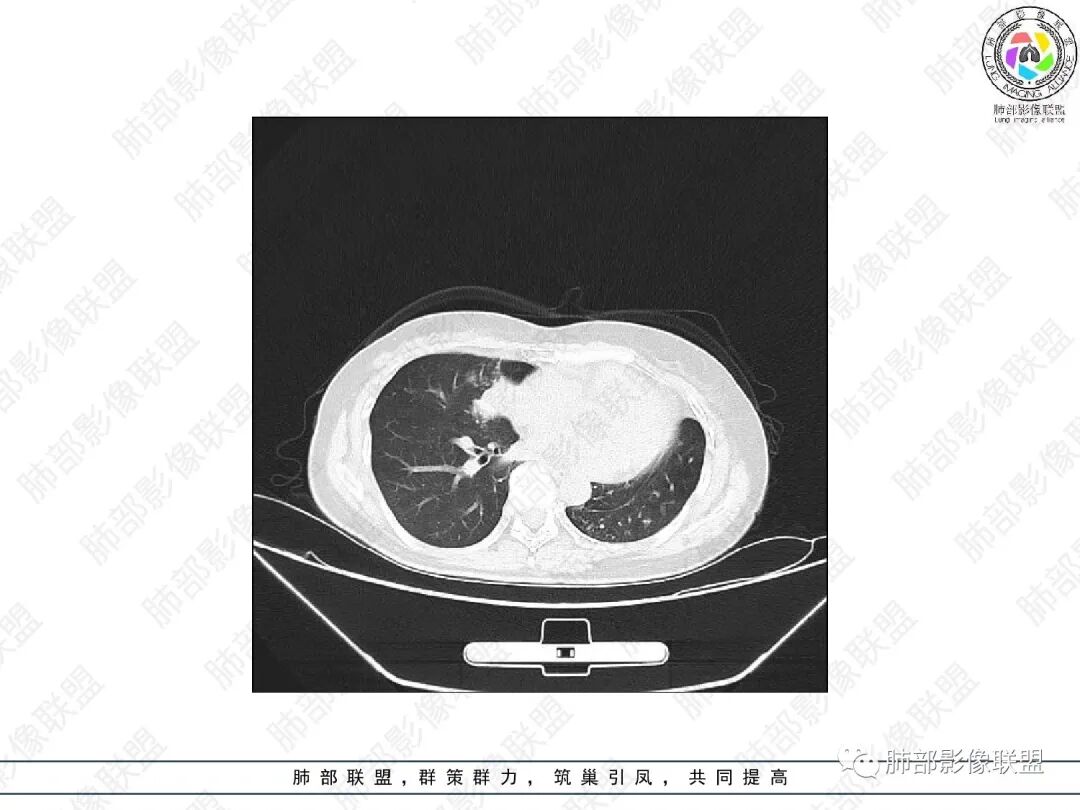

2.胸部CT:右肺上叶及中叶不规则块状影,沿支气管走行方向指套样影,支气阻塞湖嵌塞,腔内可见高密度影。灶周可见磨玻璃,外围见结节影及树芽征。左肺体积缩小,见不规则条索影、胸膜增厚,纵隔牵拉左移。

3.综合分析:结合患者病史及胸部CT主要鉴别ABPA(右肺上叶不规则块影,指套样顺延支气管方向,抗结核治疗1年,肺部病灶仍明显)及继发性肺结核TB(右肺上叶不规则肿块,其可见高密影,边缘模糊,周围卫星灶、树芽征,沿支气管爬行)。